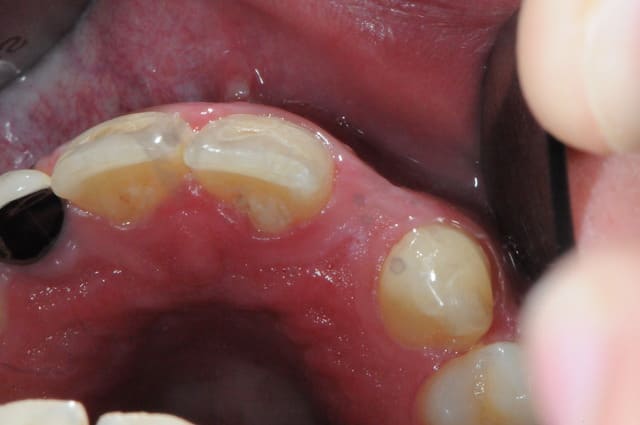

Au fait,

il faudra penser à lui enlever les restes de composite.

C'est terrible cette manie des ortho, ils ne s'appliquent jamais pour enlever les restes de colle à la fin des traitements.